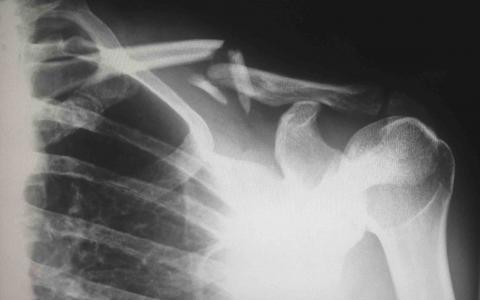

A jury in federal court awarded $15 million in damages to a woman who claimed an imaging center failed to identify her tumor for nearly 18 months, leaving her condition undetected and treated and significantly reducing her odds of surviving cancer. The jury made their decision after a four-day trial and found that the Center for Diagnostic Imaging, Inc. was responsible for the failure to identify Courtney Webster's tumor after she underwent a scan in their facility in November 2014.

Webster, along with her husband Brian, sued the Minnesota-based business in 2016 claiming that the company was negligent in diagnosing her. This resulted in severe pain and suffering as well as emotional distress. The company denied responsibility in the case, claiming they were not a medical provider. Their stance on the case ultimately cost them even more. Had the case been recoverable under malpractice guidelines, the cap would have been $1.25 million.